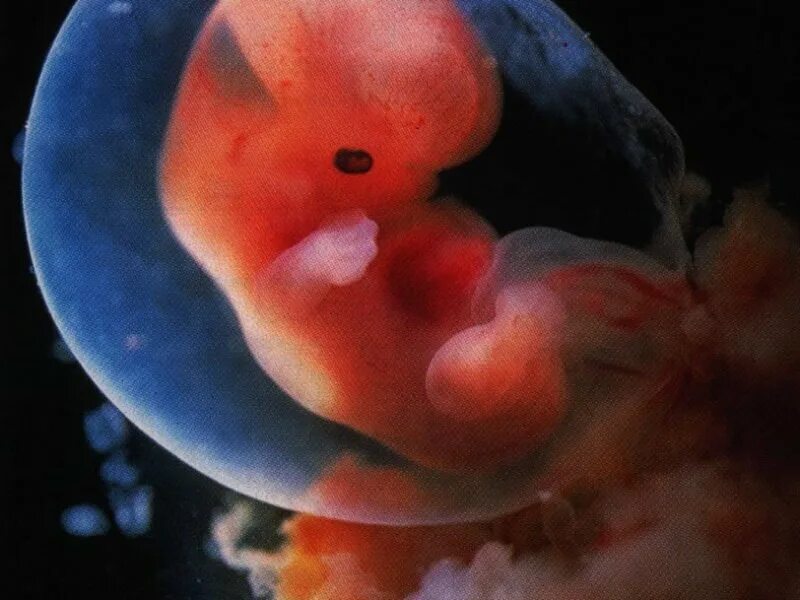

3 недели 6